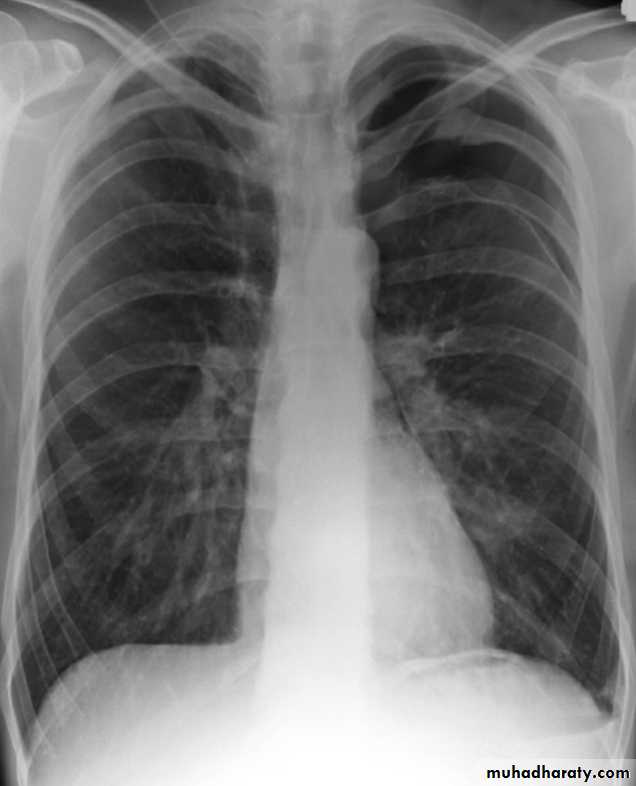

pneumothorax

53.pnuemothorax

54. pneumothorax

55. pneumothorax Right sided aspect